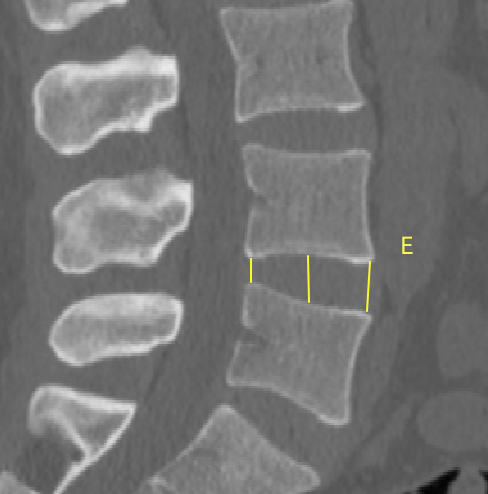

2、通过术前CT测量L4-5节段手术部位的(1)上位椎体后下角水平方向到关节突关节的距离(A);(2纤维环后缘的中点水平方向到关节突关节的距离(B);(3下位椎体后上角水平到关节突的距离C);(4上位椎体的椎弓下切迹与下位椎体椎弓上切迹连线的距离D), 6;(5)在手术节段的棘突矢状位CT层测量椎间隙高度(E), 7;(6)在手术节段的关节突关节横截面CT层测量关节突间距离(F), 8,再通过术中及术后CT判断患者椎间孔成型级别,将A-F测量数据与5级成型中的各级别成型进行相关性分析。

7  E的测量方式

undefined